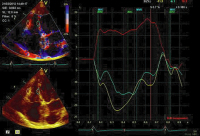

Speckletracking

Abbildung 9: Speckletracking des linken Ventrikels: Geringfügig reduzierter longitudinaler Strain (normalerweise > 16 %).

Abbildung 10: Speckletracking des linken Ventrikels: Gesteigerte radialer Strain im Querschnitt (Hyperkontraktilität).